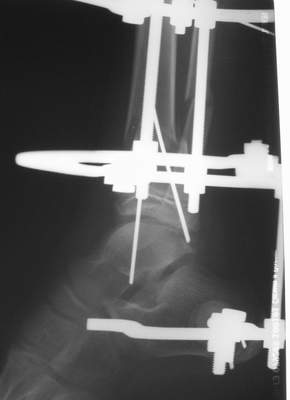

Вытяжение

|

1) з/репозиция, 2) фиксация 2 спицами, 3) аппарат, 4) фиксационные

спицы удалены...

См. аттачт.